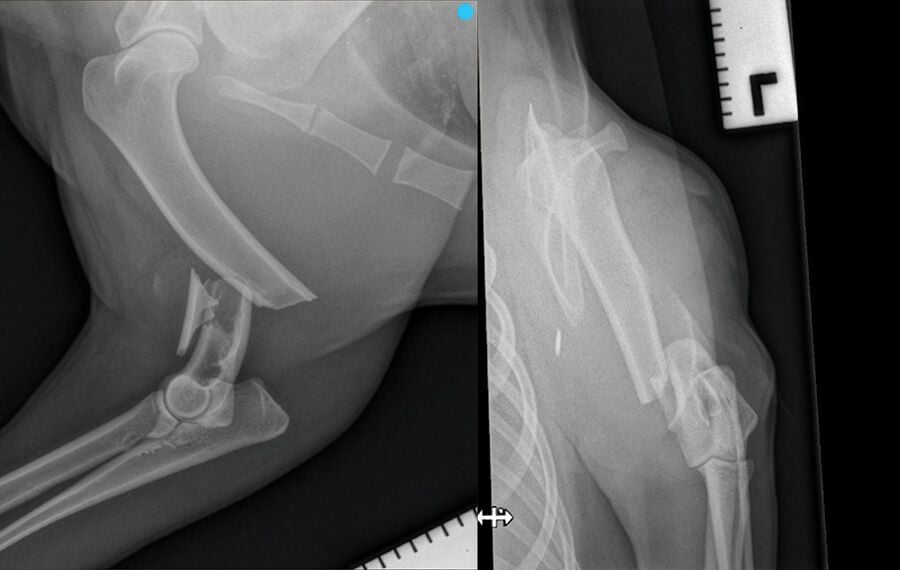

Not all breaks are the same, and identifying the specific classification of a fracture is the first step in choosing the most effective repair method.

Closed vs. Open (Compound) Fractures: A closed fracture is one where the skin remains intact. An open fracture involves the bone breaking through the skin; these are surgical emergencies due to the high risk of infection.

Comminuted Fractures: These occur when the bone has shattered into multiple pieces, often resulting from high-impact trauma like vehicle accidents.

Casts vs. Surgery: Why Internal Repair is Often Best

While a temporary splint is often helpful for initial care and transport, specialists often recommend surgical repair over traditional casting for long-term recovery.

By using internal hardware such as bone plates, screws, or interlocking nails, we can achieve: